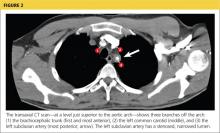

Because the diagnosis remained unclear, the patient was asked to bring the disc containing his chest CT images to the office. The radiologist, who was informed about the patient’s history and exam findings by phone, reviewed the CT images and felt there were changes surrounding the three branches off the aortic arch suggestive of inflammation, in addition to the stenosis at the left subclavian artery (see Figure 1 and Figure 2).